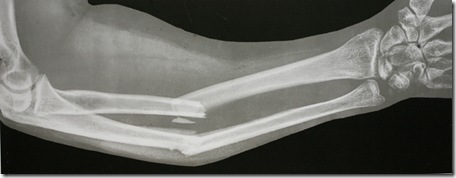

![]()

Aquesta radiografia no sóc jo, però va bé per expressar la fractura tancada de radi (radius) i cúbit (ulna) que tenia en aquell moment.